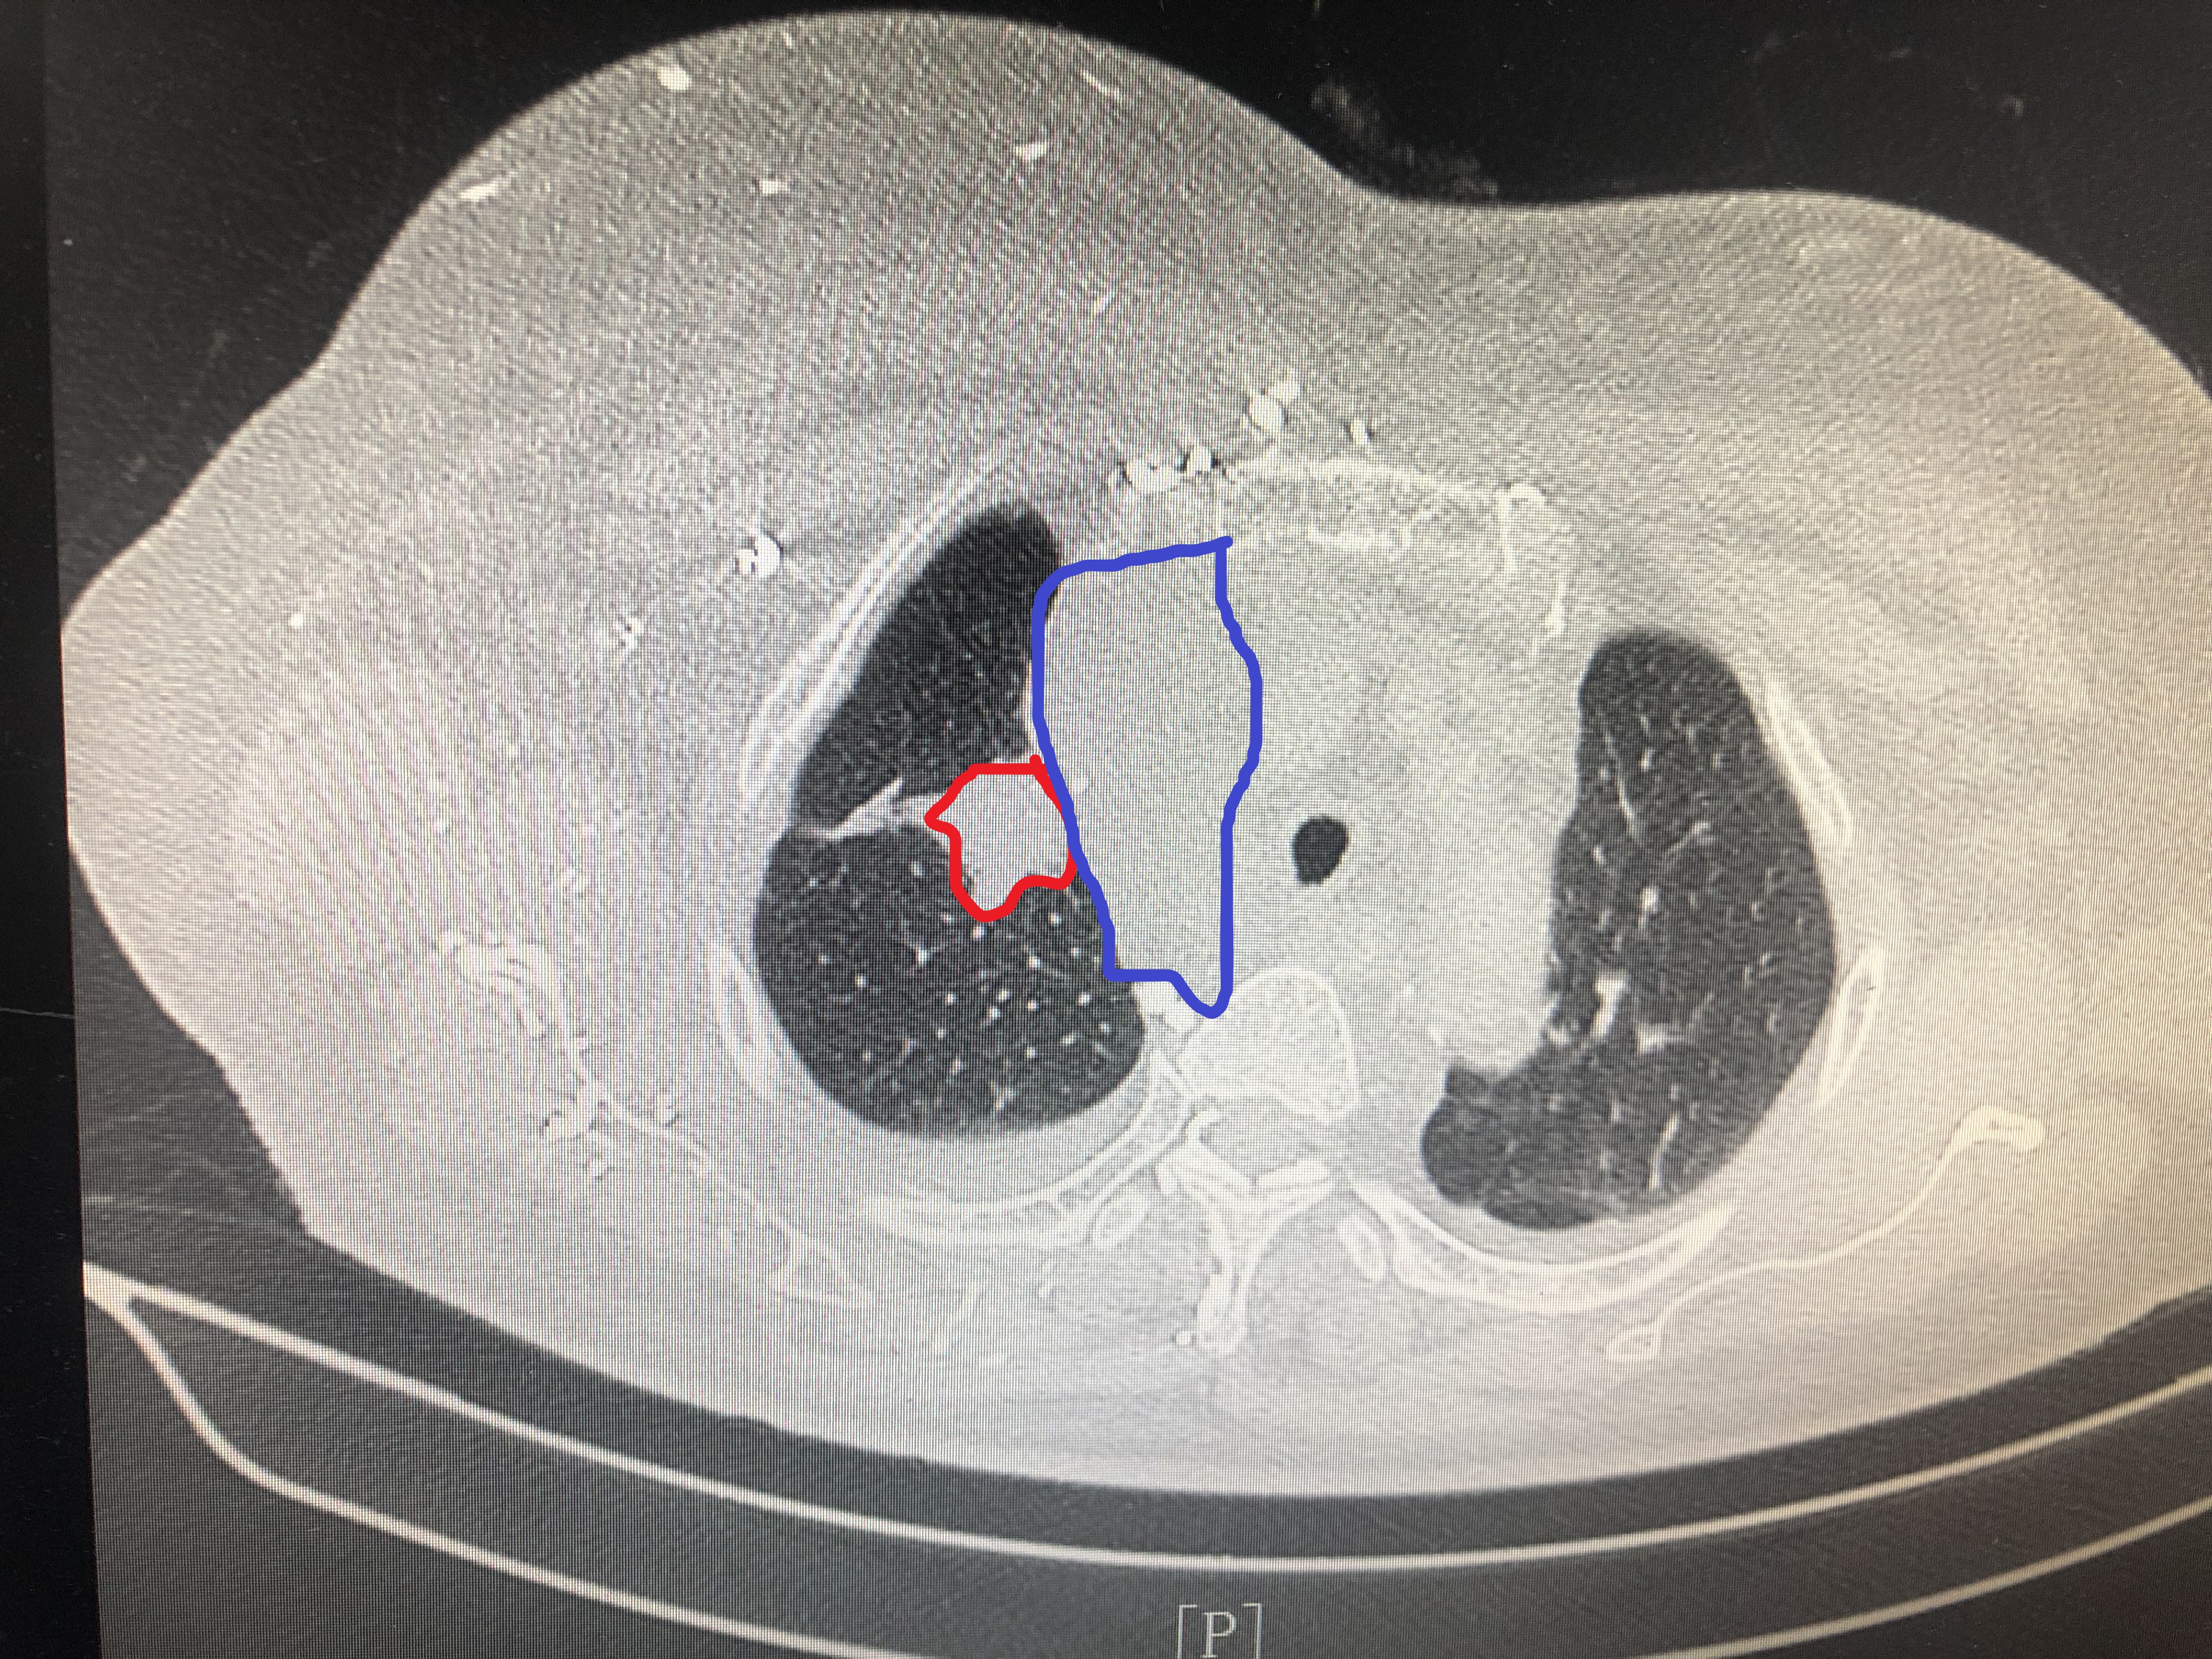

#抗击肺癌#今天上班,来了一个病人,是因为胸闷伴脸部肿胀一个月,诊断为晚期肺癌,相关的胸部CT是这样的

右上肺病灶(红色区域),纵隔淋巴肿(蓝色区域)已经压迫上腔静脉,所以病人会出现脸部肿胀。